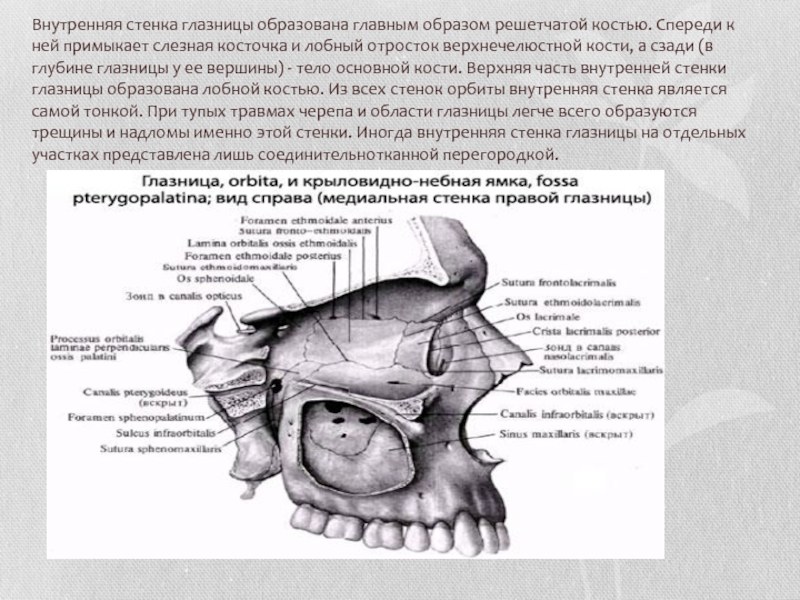

Анатомические особенности: фотографии ямок черепа, височной и подвисочной крылонебной